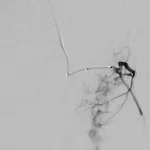

65 year old with a left femoral renal metastasis lesion. Angiograms showing vascularity of the lesion. The two annotated images show the tortuosity of the vessel supplying the lesion. The dotted orange coloured line shows the path of the vessel. It was not possible to cannulate this artery with conventional microcatheters.

Adequate catheter position attained using the Swift Ninja Catheter by Merit Medical. Final image showing reduced vascularity.